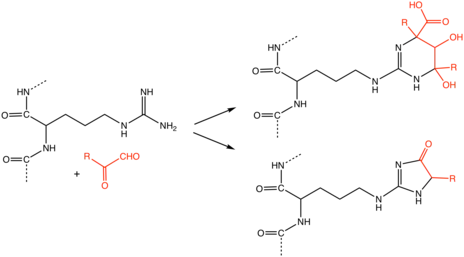

Advanced glycation end products (AGEs) are proteins or lipids that become glycated as a result of exposure to sugars.[1] They are a bio-marker implicated in aging and the development, or worsening, of many degenerative diseases, such as diabetes, atherosclerosis, chronic kidney disease, and Alzheimer's disease.[2]

Reactivity

Proteins are usually glycated through their lysine residues.[29] In humans, histones in the cell nucleus are richest in lysine, and therefore form the glycated protein N(6)-Carboxymethyllysine (CML).[29]